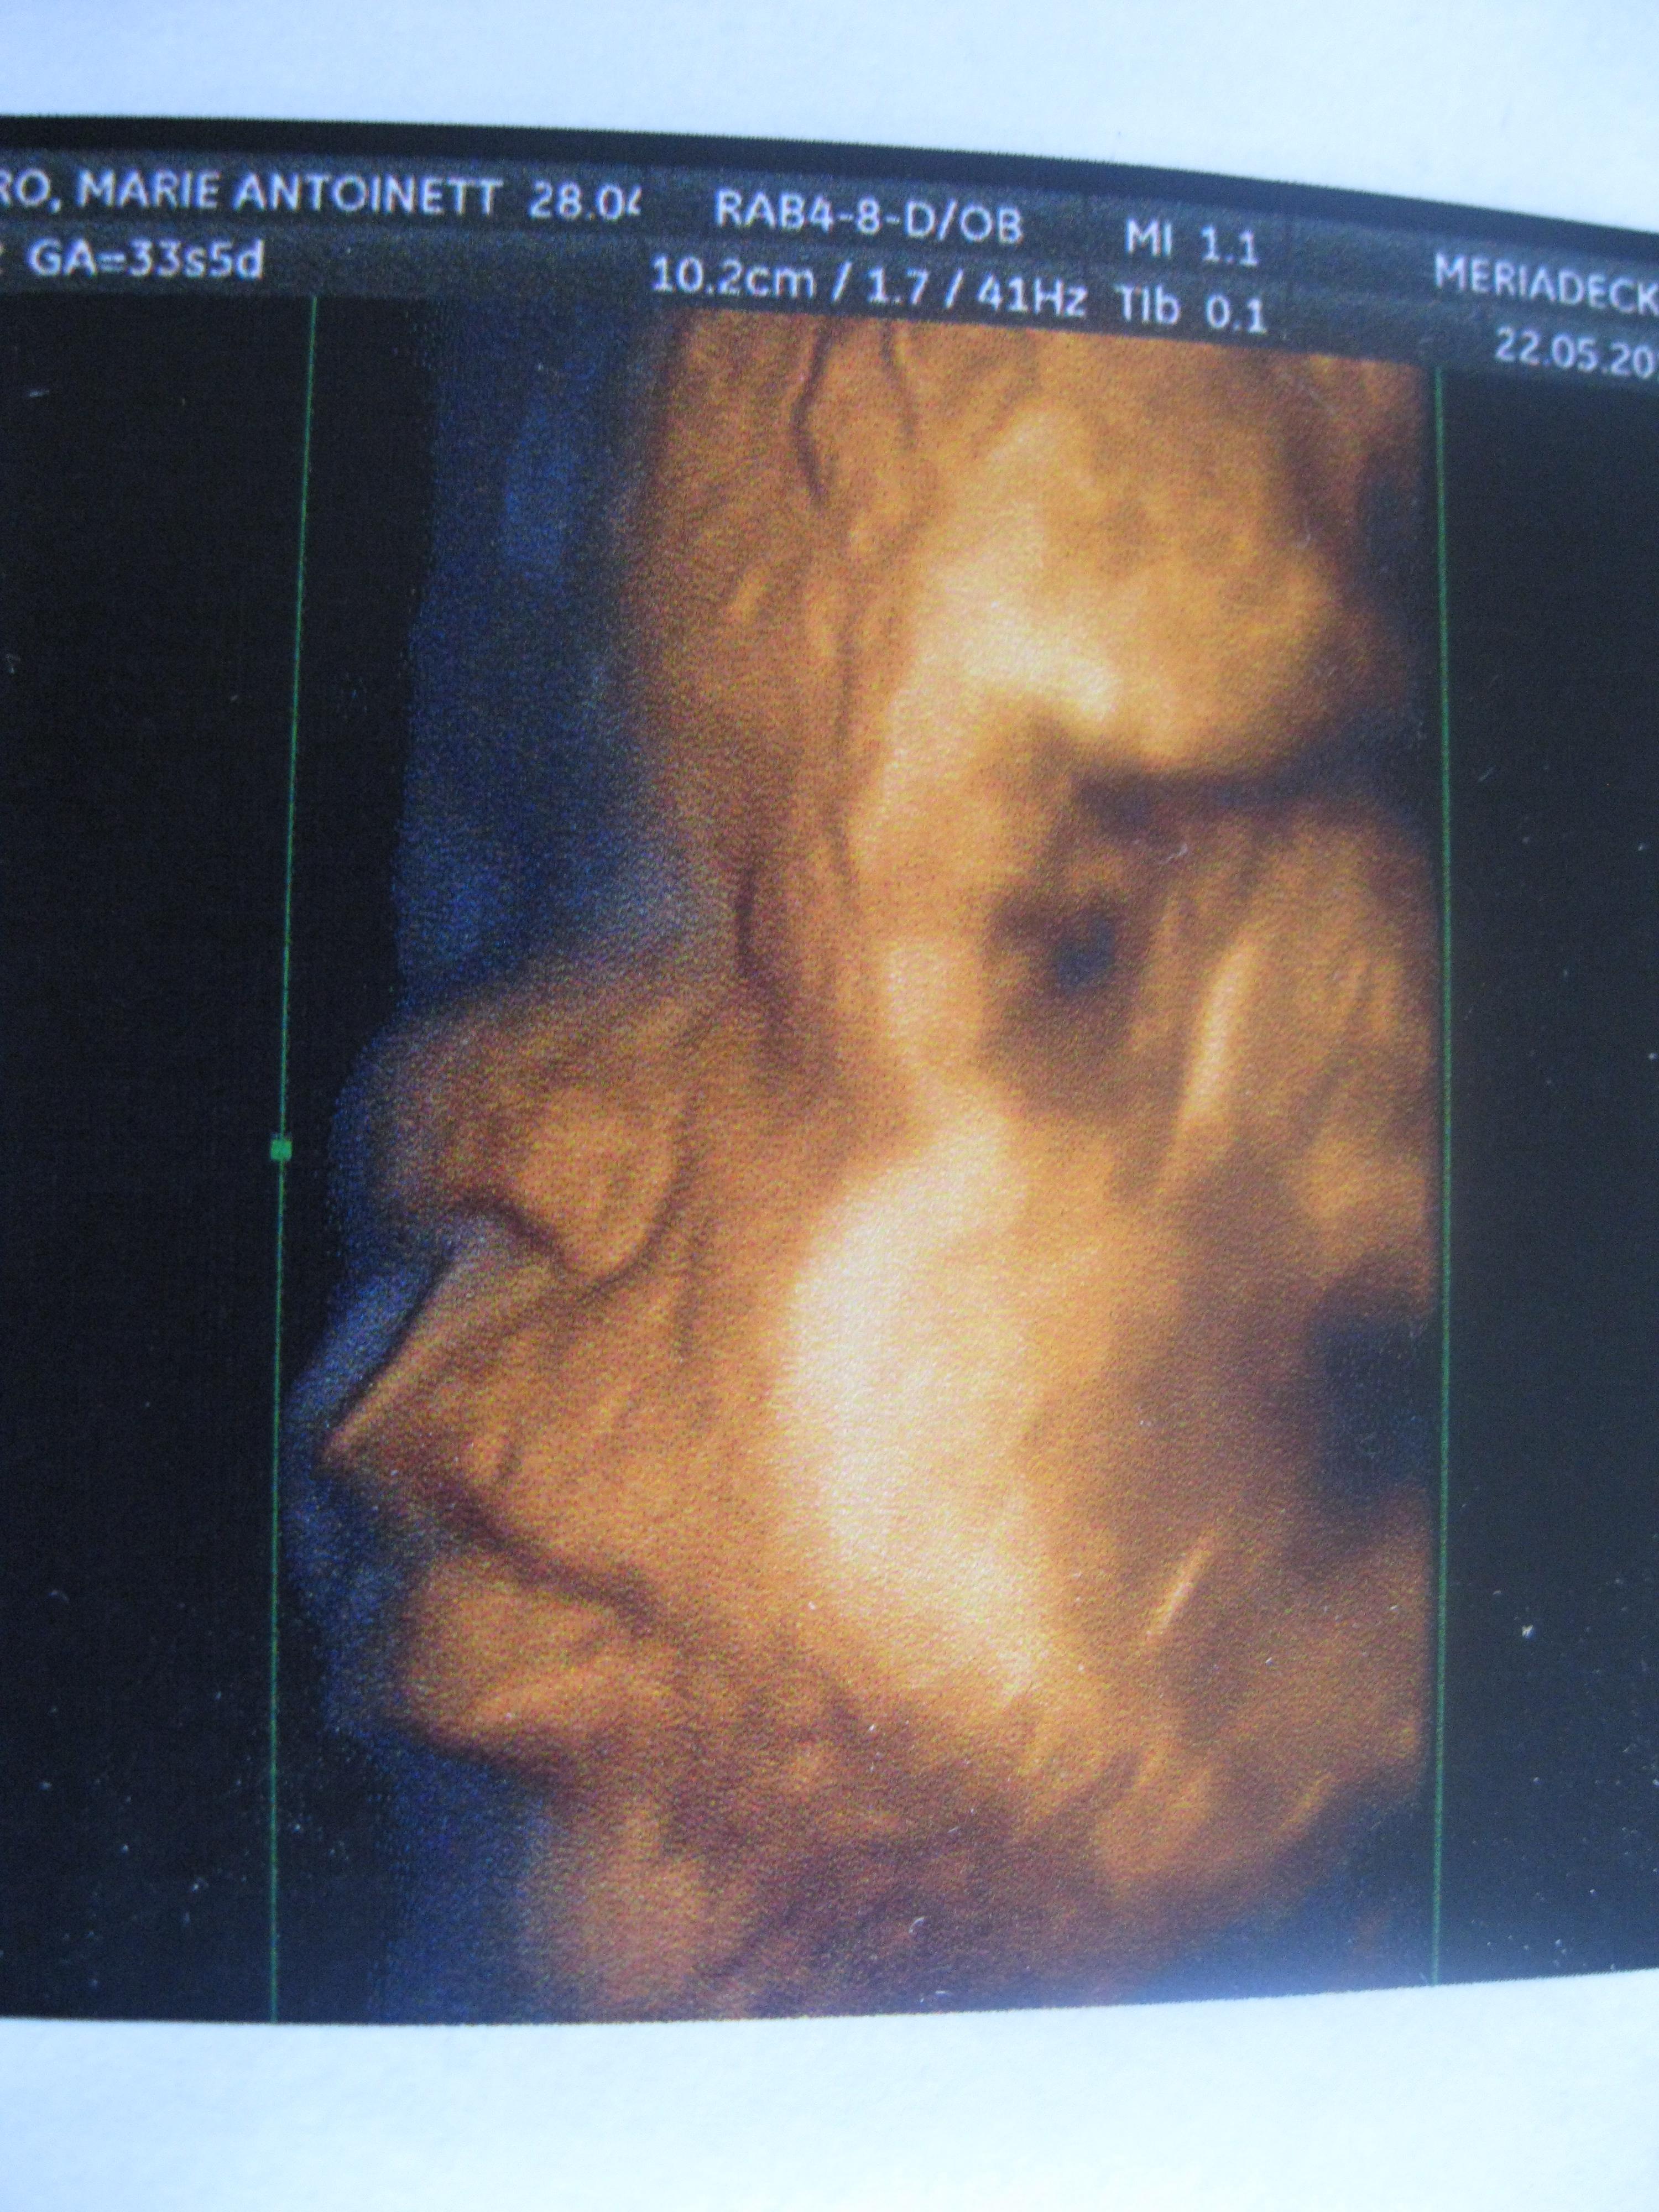

voyages des sens attend une réponse FAFCEA !!!! 28 Mai 2012 #4 oui !!!!!!!!! en plus elle a le nez de papa MDR

Doubi29 Inès, mon étoile qui brille depuis le 15juin 2012 31 Mai 2012 #8 zalmare a dit: Afficher la pièce jointe 501388 Cliquez pour agrandir... Trop chou!!!!!!!!